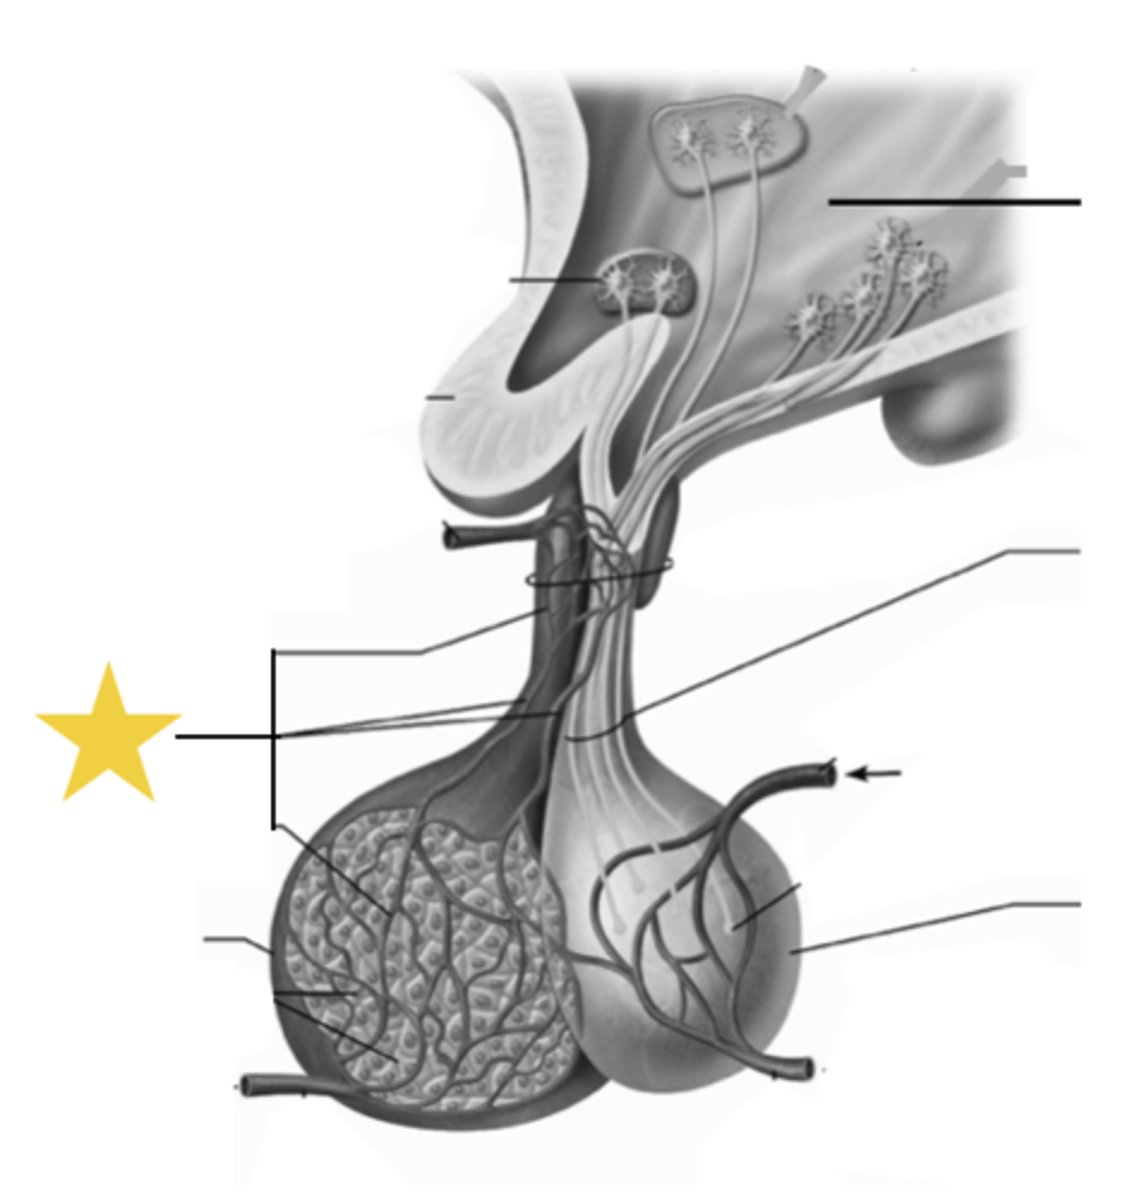

Hypothalamic-hypophyseal tract

A bundle of axons that connects the hypothalamus to the posterior pituitary, arising from the paraventricular and supraoptic nuclei.

Paraventricular nuclei

Hypothalamic nuclei that primarily produce the hormone oxytocin.

Supraoptic nuclei

Hypothalamic nuclei that primarily produce antidiuretic hormone (ADH).